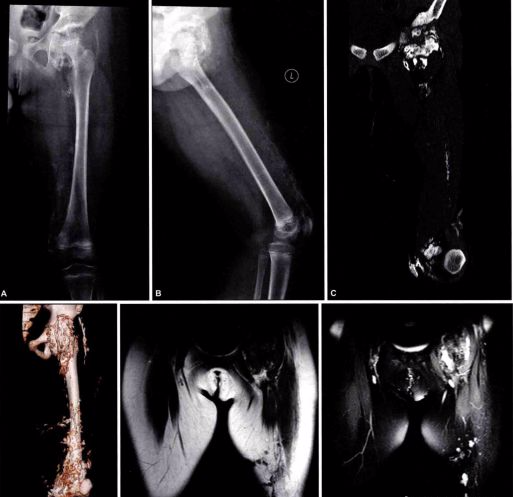

其他辅助检查:X 线照片显示肿物的软组织当中有分散钙化影。过一段时间,急性期的症状和体征消失后,肿物变小,钙化影也缩小,但密度增高。X 线片上可见柱状或不规则形态的团块状不同密度的骨化阴影,可与骨骼相连,也可完全游离。骨骼呈现失用性萎缩。

(FOP患者的X光片,异位骨化影响整个骨骼系统的形态,除局部的变形之外,脊柱也无法伸直)